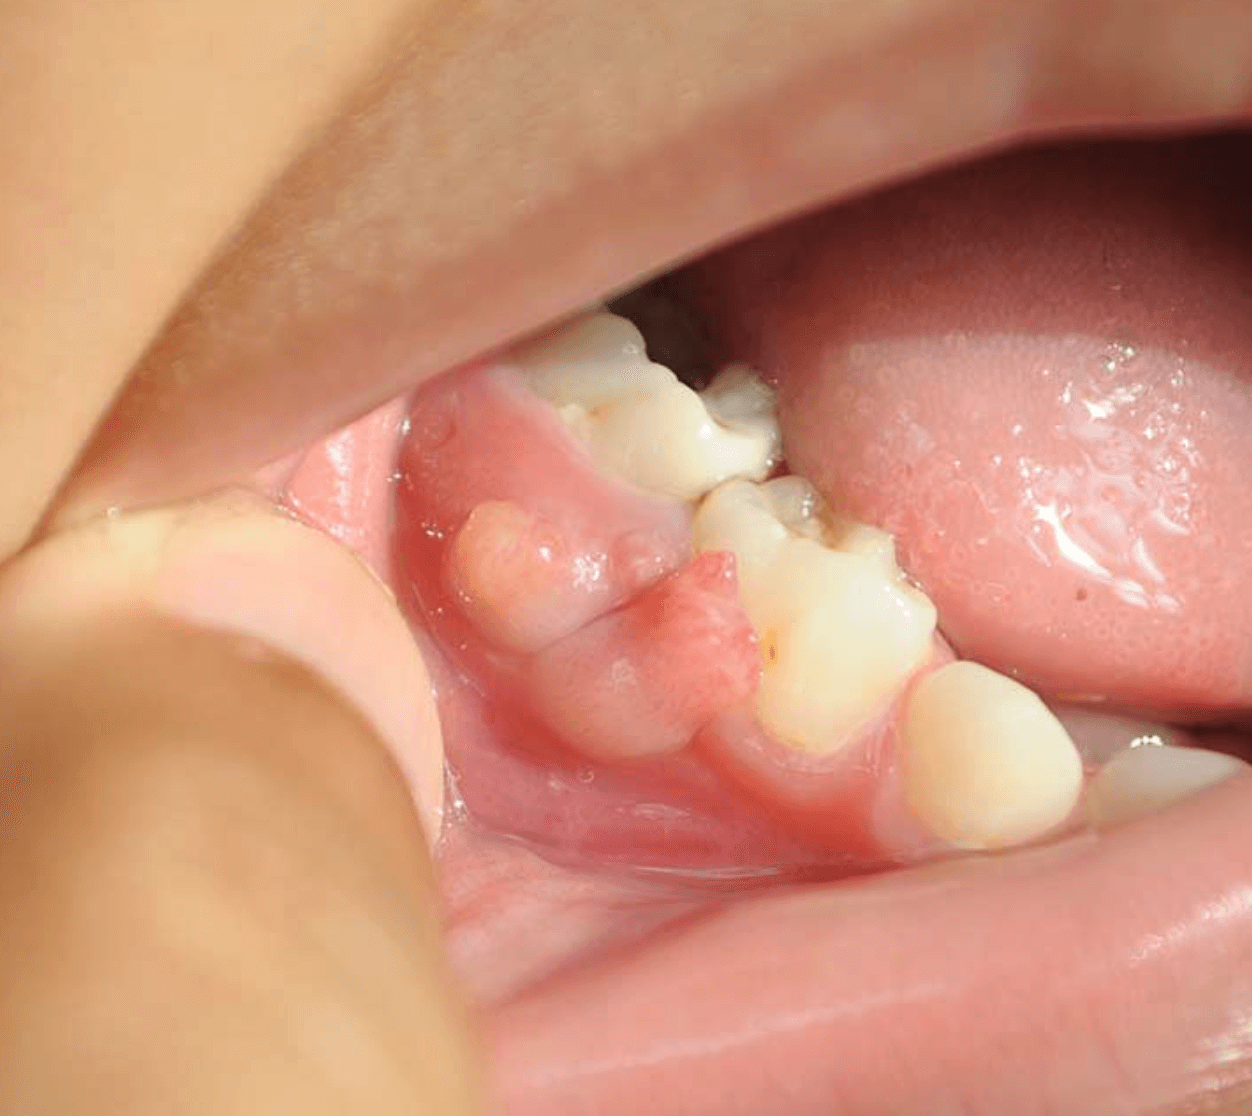

잇몸에 고름주머니 같이 잇몸이 부풀어 오른경우, 감염을 막기위해 치과의사는 항생제를 처방하고 염증인 농양이 배액될수 있도록 잇몸을 절개하고 소독할수 있습니다.

잇몸 고름주머니가 오래되고 심해서 농양으로 인해 뼈가 손상된경우 치근단 절재술을 하여 염증을 제거하고 뼈를 채우거나, 치아를 뽑고 치과적인 치료를 할수 있습니다.

- 치석을 제거 하기 위해 스케일링 실시

- 염증을 배농하기위해 잇몸 절개

- 심한경우 치아 발치후 치료